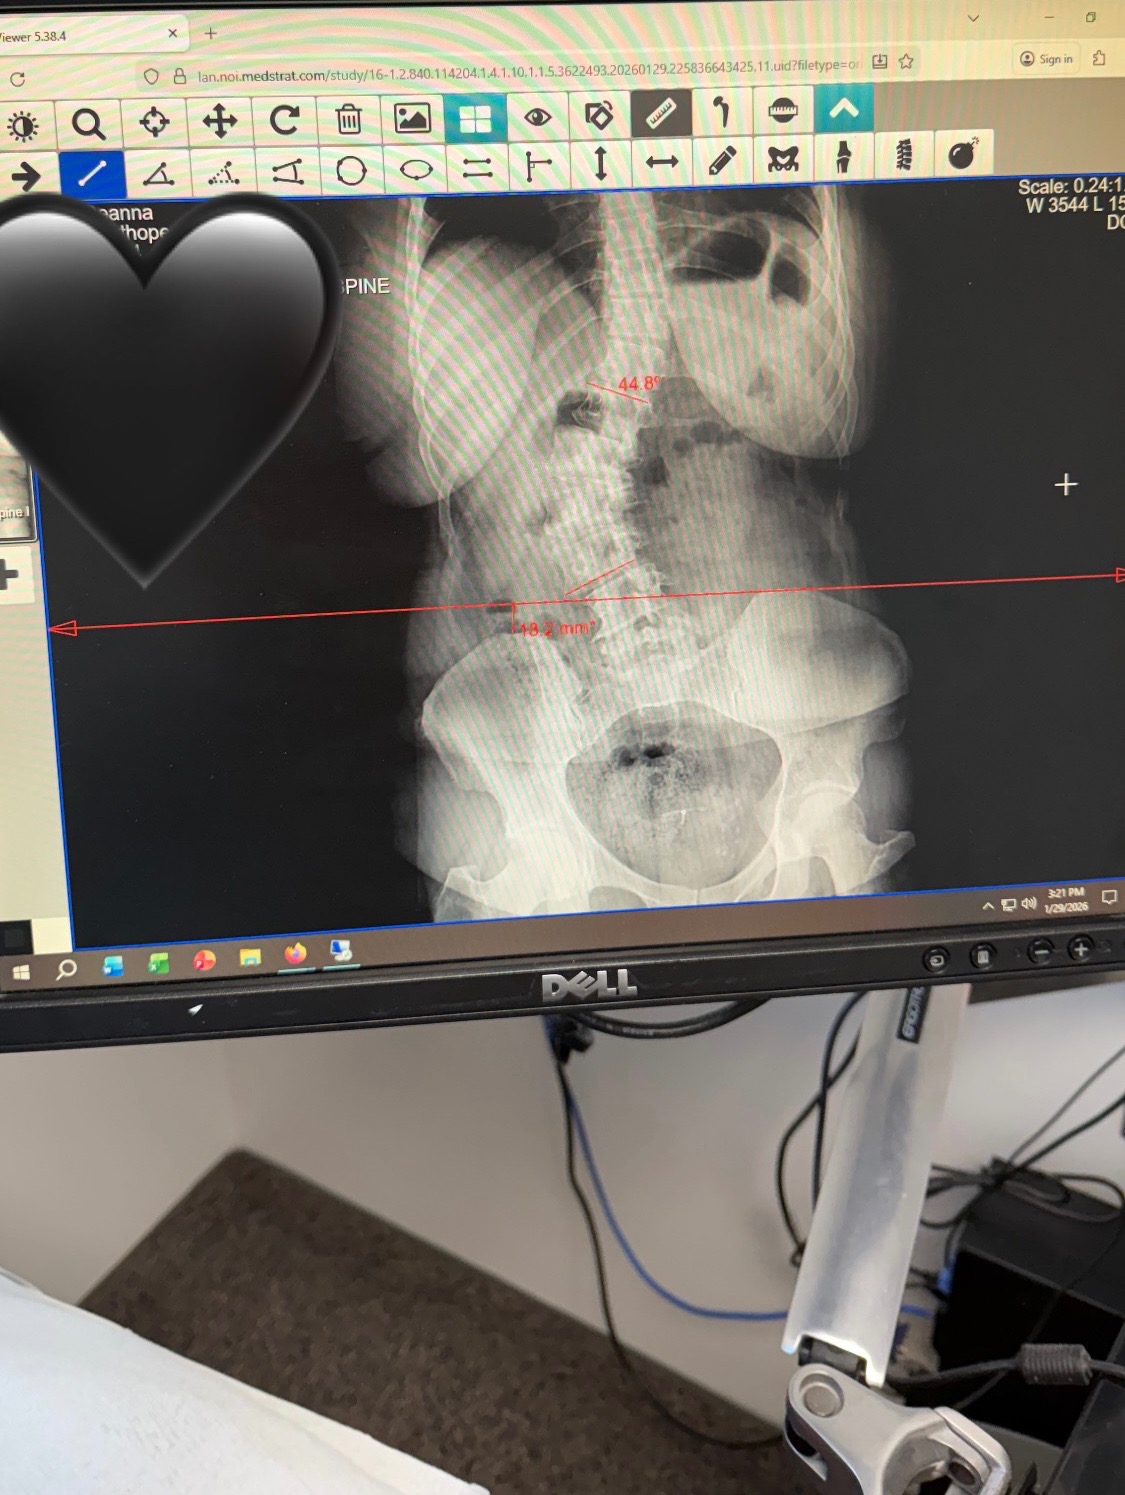

I'm 38 years old and have been suffering with lupus, POTS, and degenerative scoliosis for 13 years. It's been a long road of ups and downs, with various hospitalizations, expensive treatments, and many challenges just trying to live life at times. There have been moments of joy and good health, but each flare-up seems more difficult than the last. This time, my mobility is greatly impacted—I'm unable to sit up for long, walk, or stand for very long. The pain has left me unable to work, and I'm facing an extensive lumbar fusion surgery from T12-L4. I'm scared, but hopeful that this surgery will finally end the majority of the pain I've lived with for so long, and that I can get back to helping patients working in healthcare, which I truly miss.